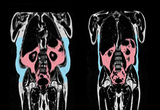

복부비만 여성 자궁내막암 위험 최대 6배 높아

- 2025-09-06 09:02

- - 기자